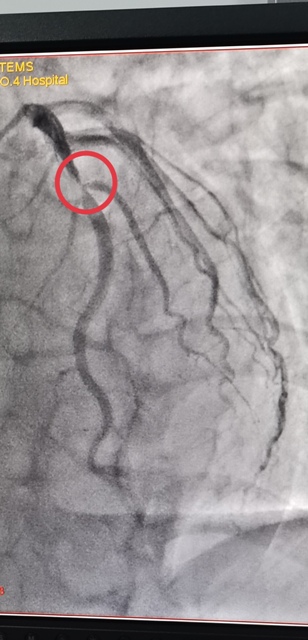

45岁的郭先生,一周前无明显诱因出现胸前区疼痛,伴有胸闷、心悸,疼痛发作时间持续10分钟后自行缓解,伴有大汗淋漓,来日韩无码 心血管内科就诊诊断为“冠心病不稳定性心绞痛”,于2021年1月3日早上10点进入导管室,实施了冠脉造影术 经皮冠状动脉内支架植入术,心内科主任王选琦主任医师介绍说,这是省四院第一例648元支架手术,手术进展顺利,患者术中、术后无不适症状,术后病症明显缓解,目前在心内科治疗观察。

陕西省第四人民医院于2021年1月1日零时执行国家组织冠脉支架集中带量采购中选结果,据悉,中选的冠脉支架产品的平均价格由原来的7500元降至648元。为确保患者在2021年1月1日当天能够使用中选产品,陕西省第四人民医院迅速贯彻省市医保局要求,已经将中选支架采购安排到位,从2021年1月1日0时开始实施新的价格标准。郭先生是蓝田人,成为新年第一个享受国家医改福利的人。